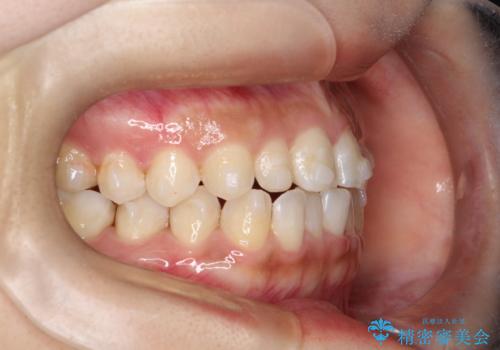

- 前歯の凸凹を主訴に来院された患者様です。

カウンセリング時に、側切歯が矮小歯であることを指摘したところ、適切な幅径での修復を希望されました。

インビザラインを用い、計画通りに歯並びを改善することができました。

矮小歯の幅径を大きくすることで、より理想的な噛み合わせを作ることができます。